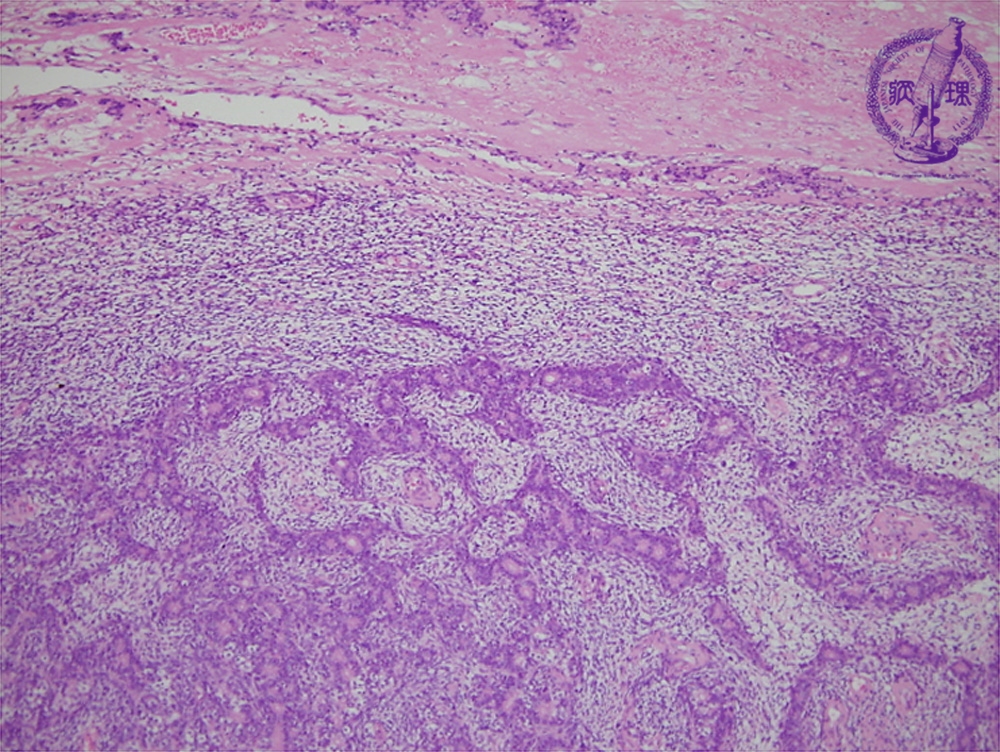

Microscopic findings (H.E. low power view): Synovial sarcoma arising in soft tissue around the major joints. Biphasic type with both mesenchymal (upper) and epithelial (lower) elements, but a monophasic type with an either element is also reported.